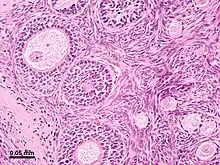

Microanatomy

The surface of the ovaries is covered with a membrane consisting of a lining of simple cuboidal-to-columnar shaped mesothelium,[7] called the germinal epithelium.

The outer layer is the ovarian cortex, consisting of ovarian follicles and stroma in between them. Included in the follicles are the cumulus oophorus, membrana granulosa (and the granulosa cells inside it), corona radiata, zona pellucida, and primary oocyte. Theca of follicle, antrum and liquor folliculi are also contained in the follicle. Also in the cortex is the corpus luteum derived from the follicles. The innermost layer is the ovarian medulla.[8] It can be hard to distinguish between the cortex and medulla, but follicles are usually not found in the medulla.

Follicular cells are flat epithelial cells that originate from surface epithelium covering the ovary. They are surrounded by granulosa cells that have changed from flat to cuboidal and proliferated to produce a stratified epithelium.